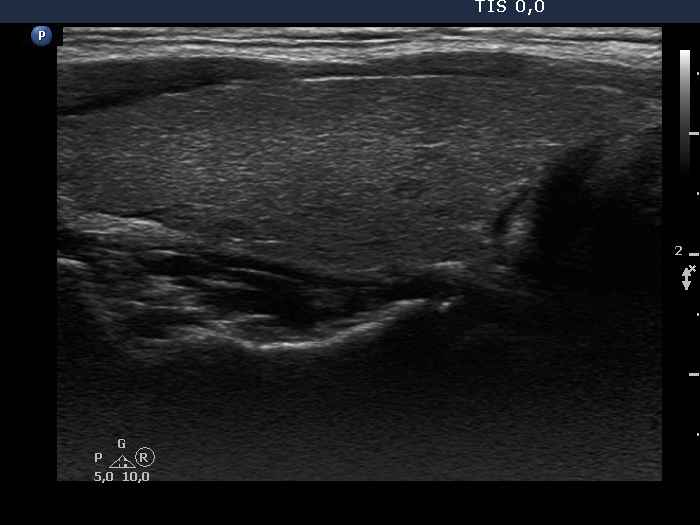

The composition of the nodule - case 753 (ultrasonographic picture 7)

Left lobe, longitudinal scan.